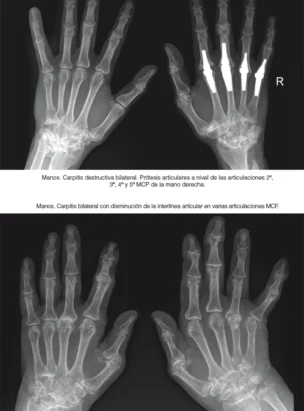

Artritis Reumatoide